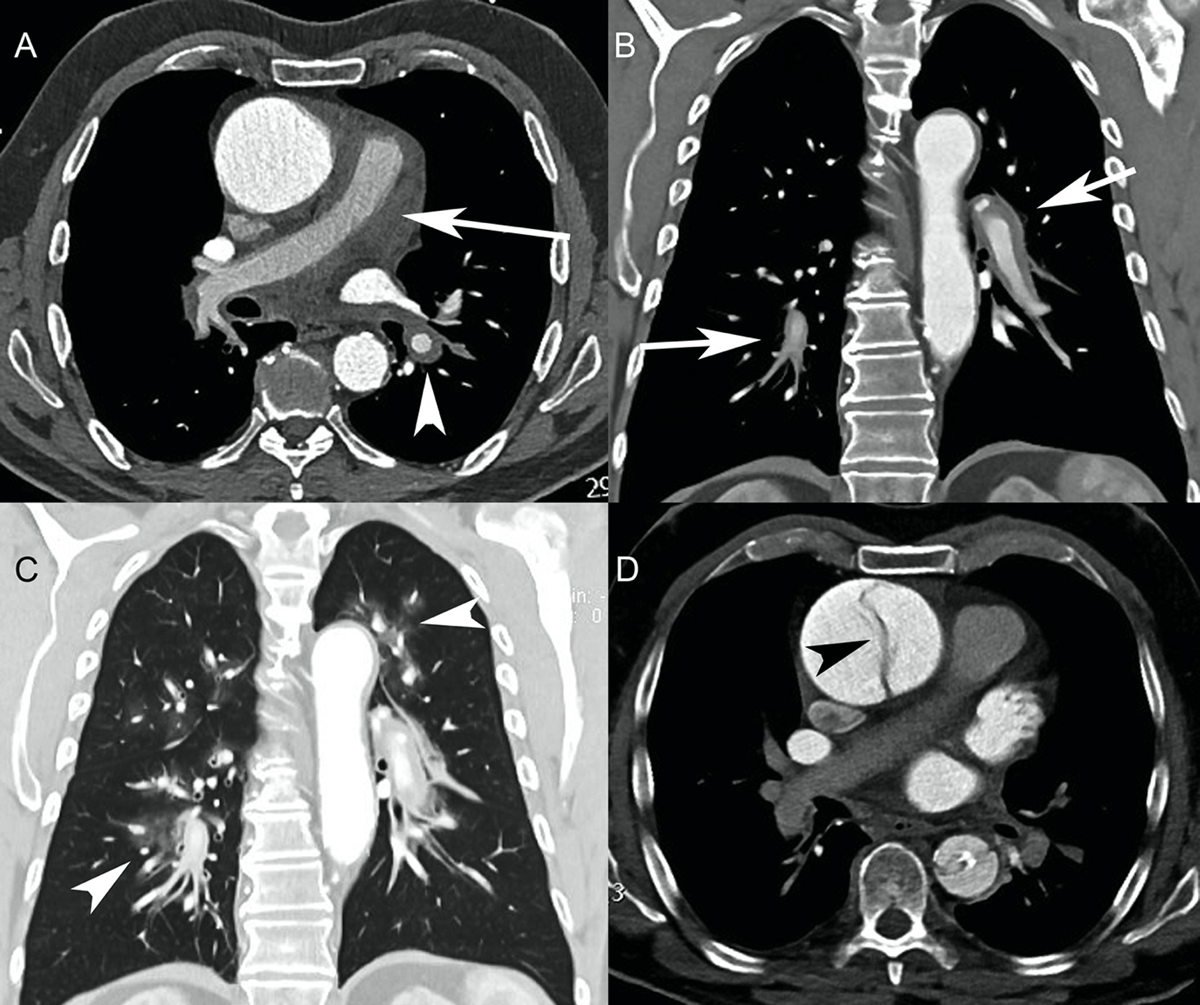

Figure 4

Patient 4. (A) Initial axial CT angiography (CTA) showed an aortic aneurysm. No intimal flap was seen. However, the contour of the ascending aorta was irregular. There was circumferential thickening of the pulmonary arterial wall (arrow), extending into the right and left pulmonary arteries (arrowhead), suggestive of pulmonary artery intramural hematoma. (B) Initial CTA (coronal reformation) showed the extension of the pulmonary artery intramural hematoma to the interlobar and segmental pulmonary arteries (arrows). (C) Initial CTA (coronal reformation, pulmonary window) revealed ground-glass opacities around the pulmonary arteries consistent with alveolar hemorrhage (arrowheads). (D) Second axial CTA performed two days later showed an intimal flap of the ascending aorta, suggestive of Stanford type A acute aortic dissection (arrowhead). Both the pulmonary artery intramural hematoma and alveolar hemorrhage had resolved.